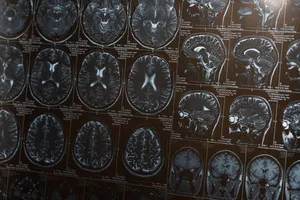

MRI(자기 공명영상) 검사는 강력한 자기장과 라디오파를 이용해 우리 몸속을 생생하게 들여다보는 최첨단 영상 검사입니다. 뇌, 척수, 관절 등 다양한 부위의 질환을 조기에 발견하고 정확하게 진단하는 데 필수적입니다.

MRI 검사는 CT 검사보다 훨씬 더 세밀한 영상을 제공하여, 마치 우리 몸의 지도를 보듯이 각 조직과 기관의 미세한 차이까지 파악할 수 있습니다. 뇌종양, 뇌출혈, 척추 디스크, 관절염 등 다양한 질환의 정확한 위치와 크기를 정밀하게 확인하여, 환자에게 꼭 맞는 최적의 치료 계획을 세우는 데 결정적인 역할을 합니다.

1. 뇌 질환

· 두통, 어지럼증

만성적인 두통이나 원인불명의 어지럼증이 지속될 때 뇌종양, 뇌혈관 질환 등을 확인하기 위해 MRI 검사를 시행합니다.

· 뇌졸중, 뇌경색

뇌혈관이 막히거나 터져 발생하는 뇌경색의 정확한 위치와 크기를 파악하여 신속한 치료를 위한 중요한 정보를 제공합니다.

· 뇌종양

뇌종양의 종류, 크기, 위치를 정확하게 파악하여 수술 계획을 세우고 치료 효과를 평가합니다.

· 다발성 경화증

뇌와 척수의 신경세포가 손상되는 탈수초성 질환으로, MRI 검사를 통해 병변을 확인하고 진단합니다.